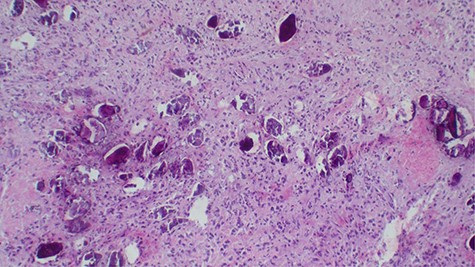

Laboratory investigations revealed a low platelet level of 53 per microliter and hemoglobin level of 10.7 g/dl. Renal profile, white blood count and serum electrolytes were within normal range. Computed tomography intravenous urogram revealed a large heterogeneous mass, measuring 5.5 × 4.5 cm at the right superolateral aspect of the urinary bladder with ipsilateral hydronephrosis and hydroureter. Bone scan study was unremarkable. Urothelial cell carcinoma of the urinary bladder was clinically suggested as the most likely differential diagnosis. Cystoscopy was done under spinal anesthesia, which revealed a solid mass with areas of necrosis at the anterior bladder wall. The biopsy was taken whose histological evaluation revealed a high-grade malignant mesenchymal tumor made up of oval or spindle cells with osteoid formation in many areas of the lesion (Fig. 1). No definite carcinomatous component was appreciated. The tumor was strongly positive for vimentin immunohistochemistry staining (Fig. 2) and negative for cytokeratin 20. Calcified schistosomal ova were also seen (Fig. 3).

Calcified schistosomal ova near or within the tumor (H&E ×400).

A number of risk factors for primary extraskeletal osteosarcoma have been reported in the literature. Radiotherapy, schistosomal infection, trauma, diverticulitis, use of chemotherapy agents such as cyclophosphamide and frequent urinary tract infections have been implicated [1, 6]. Our patient had schistosomiasis (Fig. 3) which might have been the predisposing risk factor.